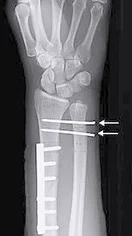

Intra-articular Distal Radius Fracture

- treated by anatomical open reduction, internal fixation and early mobilization

- Anatomical Open reduction and internal fixation by Plating and screws( best fixation)

- Plating of radius

- Reduction of distal radio-ulnar joint (+/- Fixation)